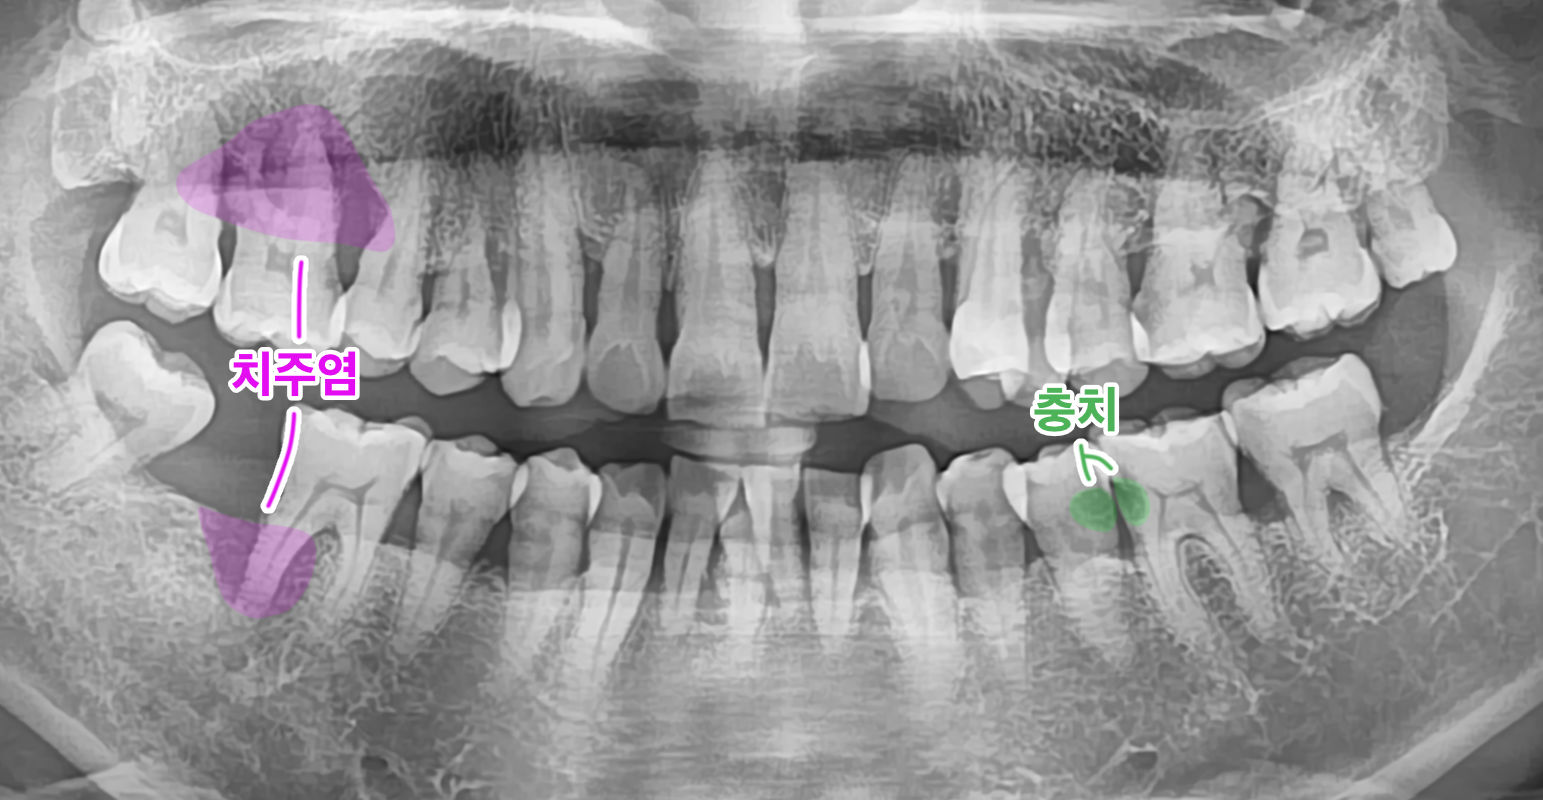

전체 치아의 상태를 한꺼번에 확인할 수 있는 장점을 살려, 파노라마 사진 한 장으로 치주염의 전체적인 상태 그리고 충치의 대략적인 갯수를 확인할 수 있습니다